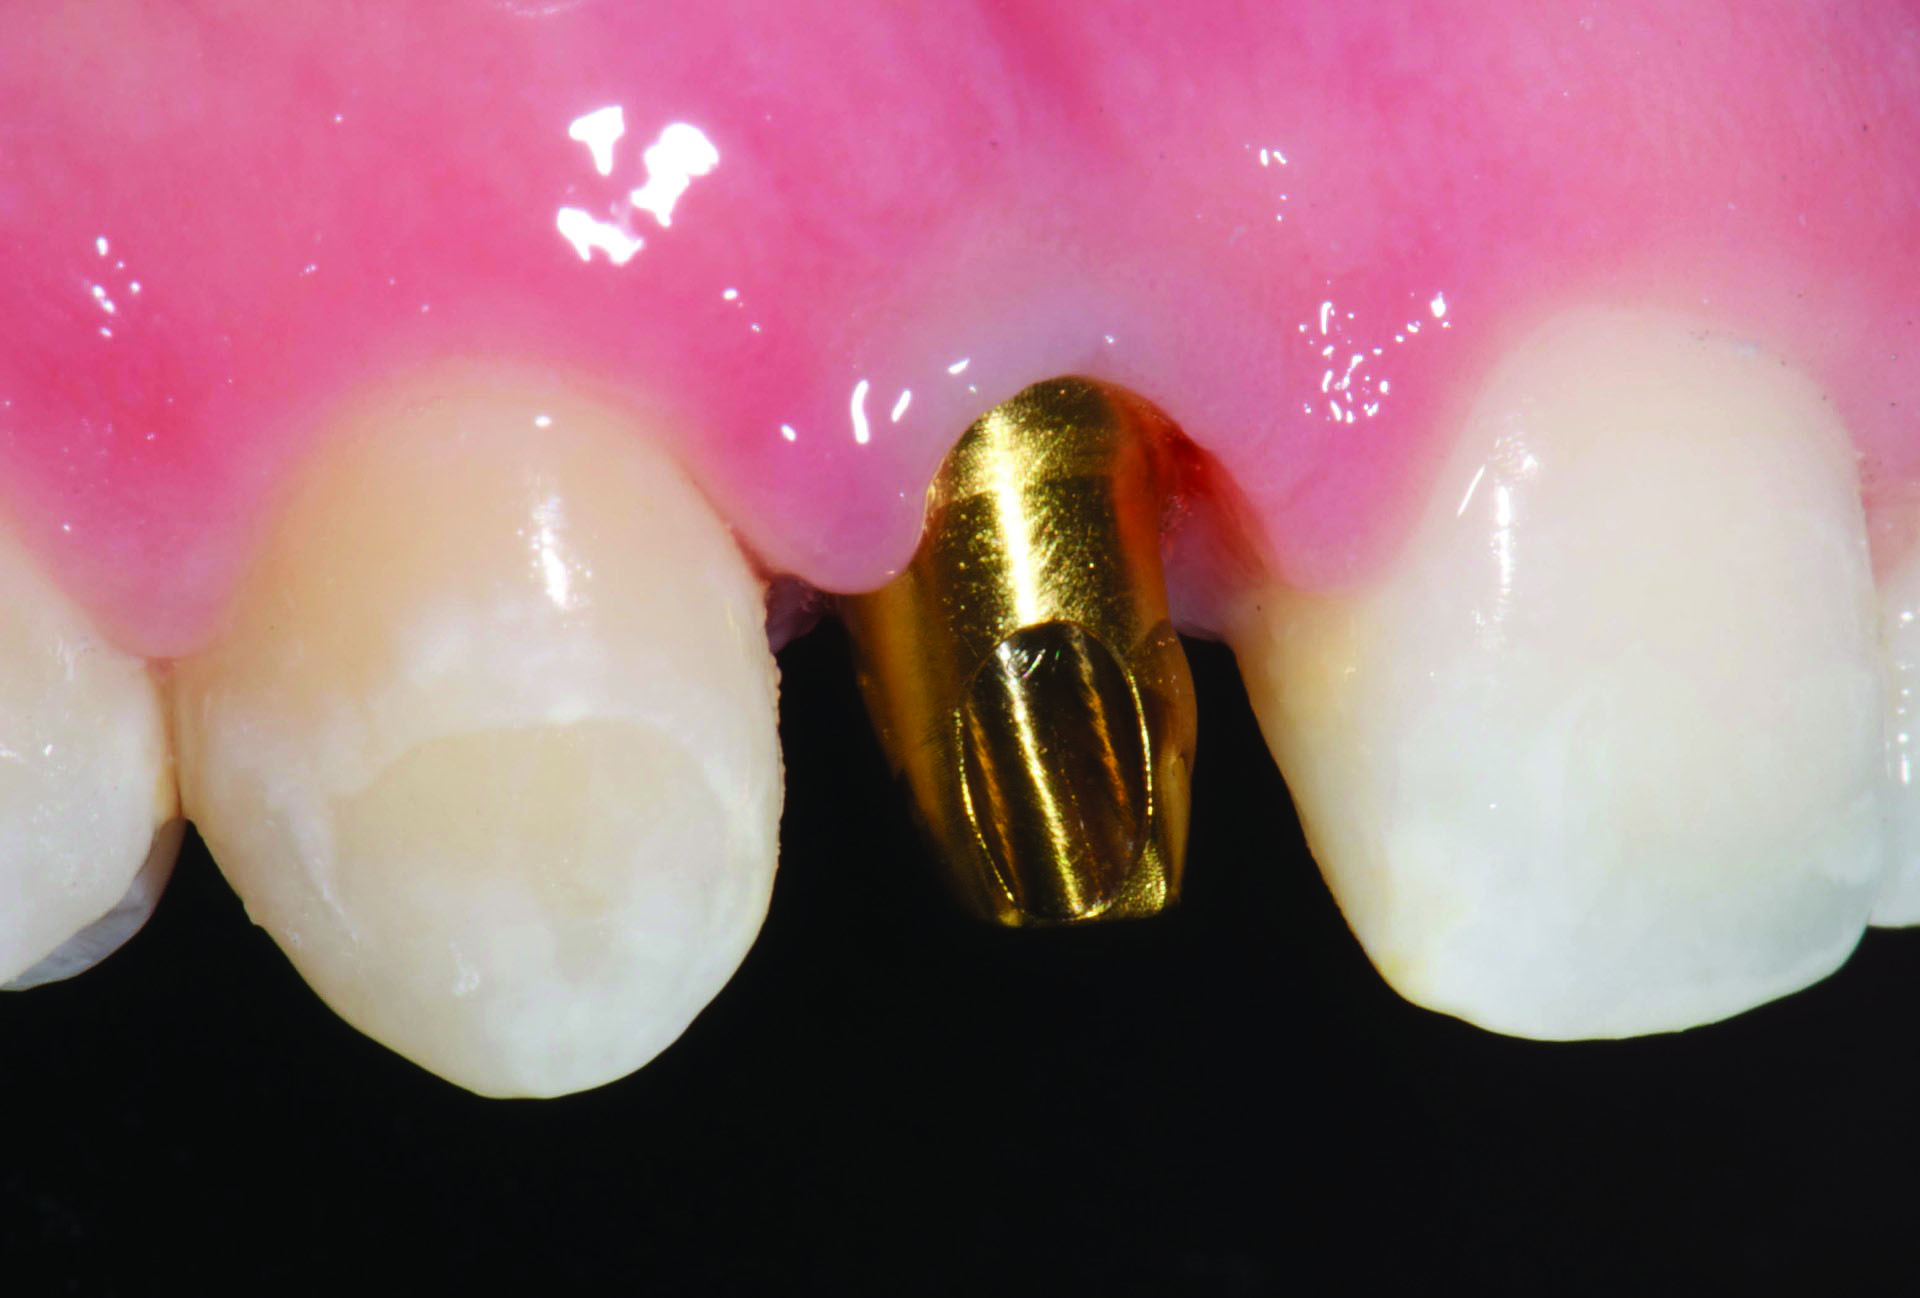

Titanium show-through of the gingival can also be an issue. Figure 2 demonstrates a titanium abutment that is visible through the soft tissue of an anterior implant restoration. Results of the aforementioned survey disclosed that 42% of clinicians place the abutment margins 1 mm subgingival and the remainder are placed 0.5 mm subgingival (33%) or equigingival (25%).1 Placing the margins deeper within the sulcus may help to hide the titanium; however, margins placed 1 mm and 3 mm subgingivally had about 12 times or 24 times more undetected excess cement, respectively, than equigingival margins.5

Fig 2. Titanium abutment is visible through the soft tissue of an anterior implant restoration on the maxillary left lateral incisor.

Figure 2